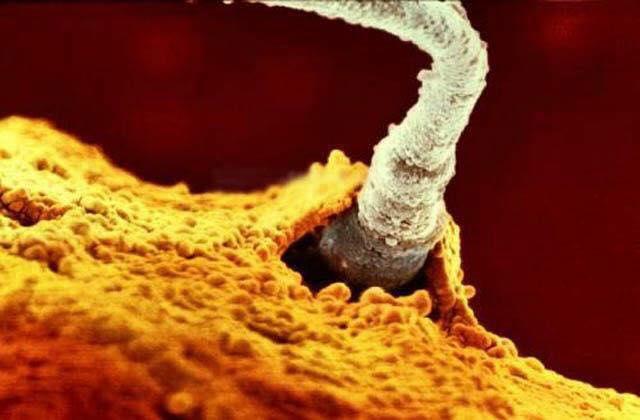

Entrada do espermatozoide no óvulo

A fecundação